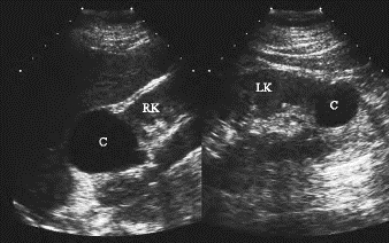

图29-7 肾囊肿声像图

右肾上极、左肾下极无回声区(C),边界清楚,内部清晰,向肾外突出